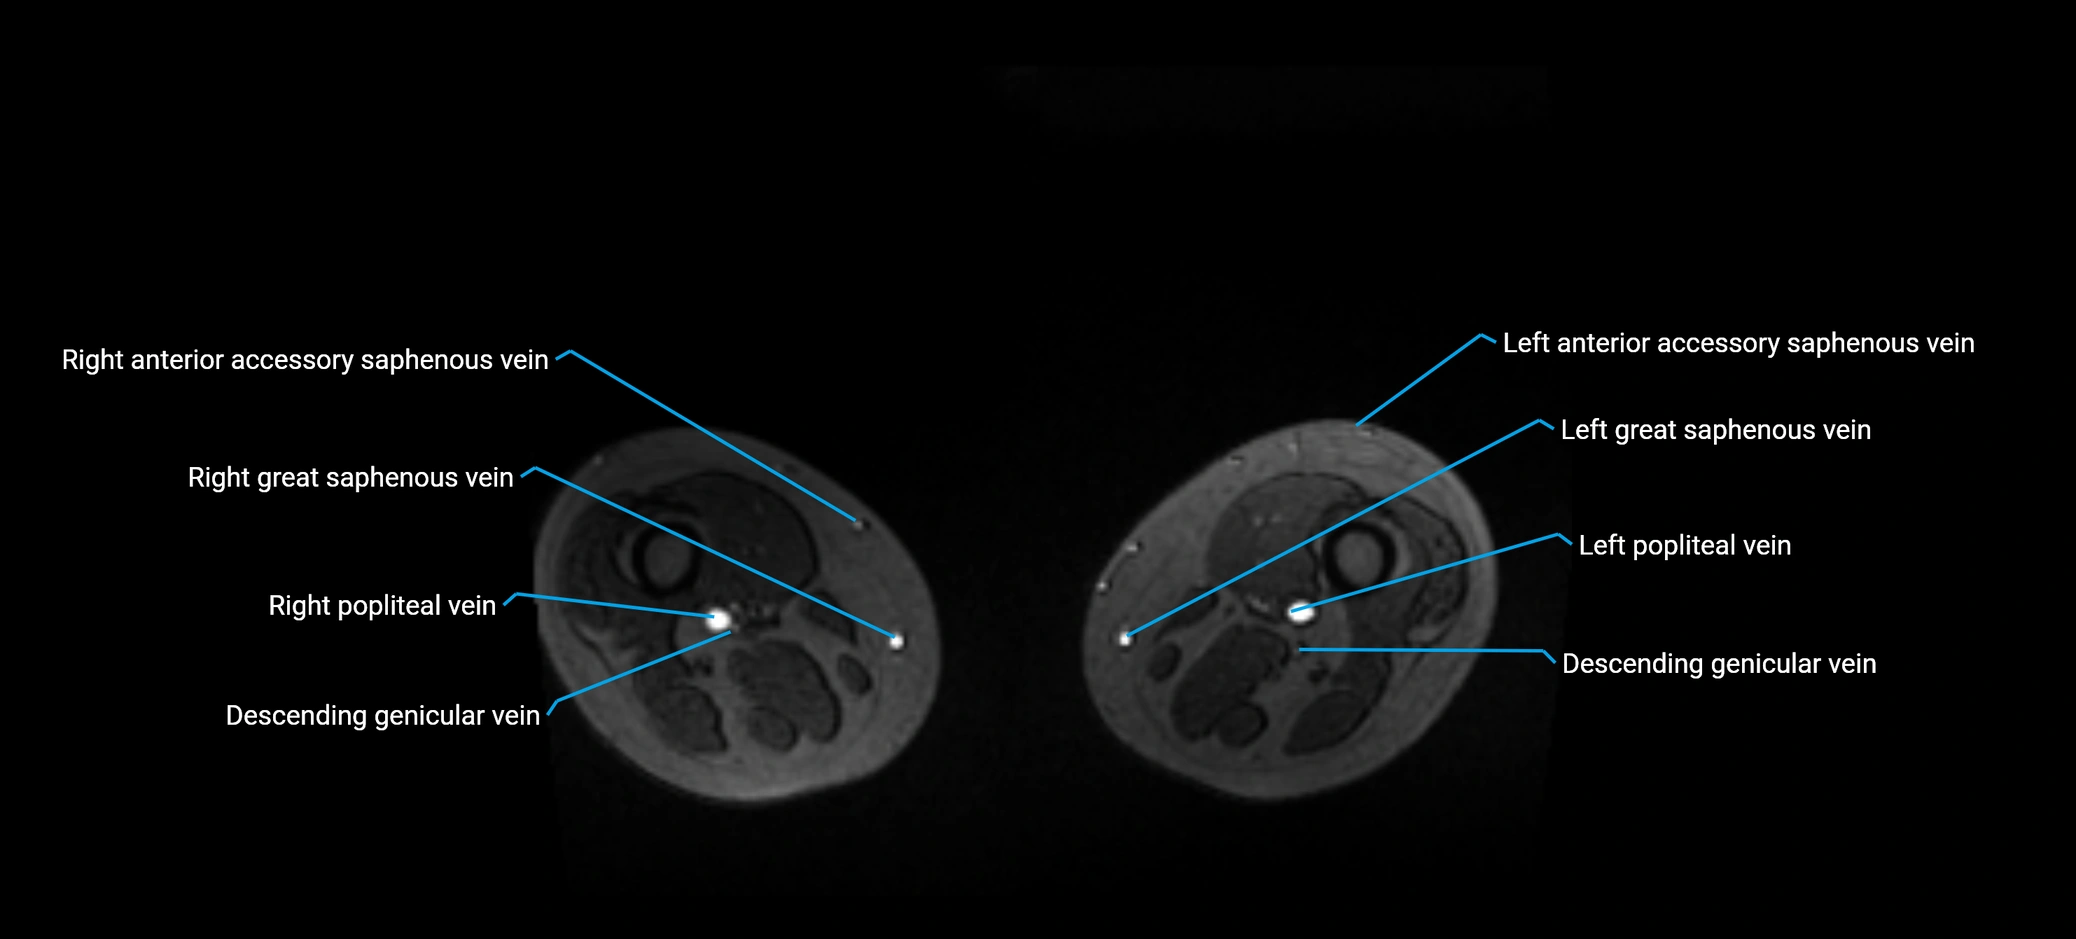

MRI image

image